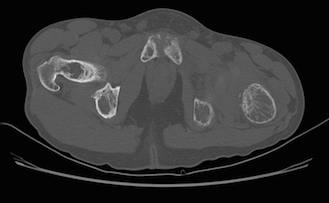

Alteração difusa do trabeculado ósseo em toda a região avaliada, associada a focos de reabsorção óssea subcondral na sínfise púbica e na borda anterior das sacroilíacas, relacionados à doença de base (hiperparatireoidismo).

Associam-se sinais de fratura patológica no colo do fêmur esquerdo, com reabsorção óssea junto ao foco de fratura e desalinhamento entre os fragmentos, com sinais de derrame articular do quadril homolateral, de aspecto reacional.